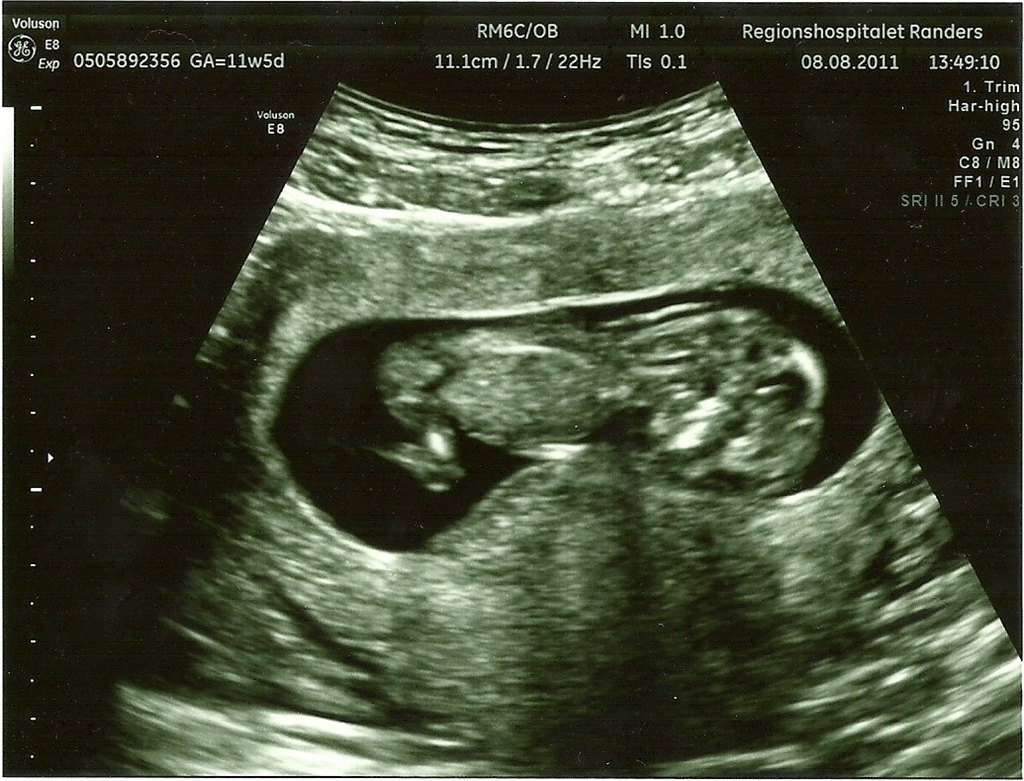

Den 9 september kl 10.00 skal jeg til første scanning med maven og vi glæder os sindssygt meget!

Jeg kan regne frem at jeg så er 12+2 så det er helt perfekt

Hvornår var I til scanning og vil I dele jeres flåååårtte NF-billeder så jeg rigtig ka glæde mig endnu mere